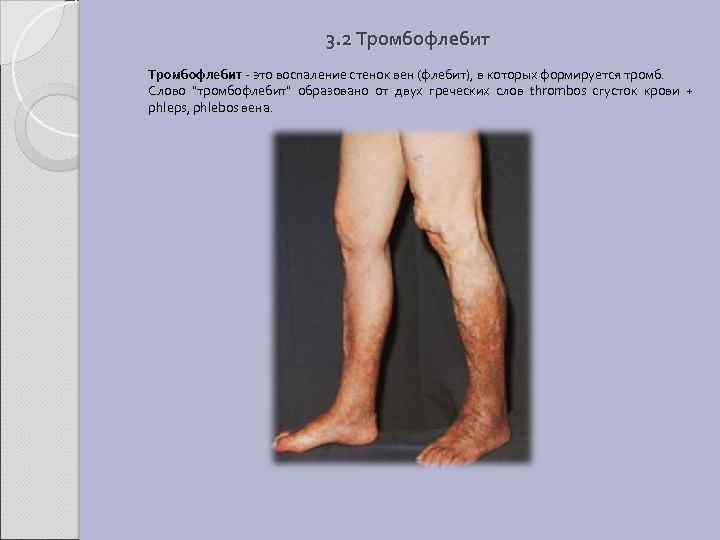

3. 2 Тромбофлебит - это воспаление стенок вен (флебит), в которых формируется тромб. Слово "тромбофлебит" образовано от двух греческих слов thrombos сгусток крови + phleps, phlebos вена.